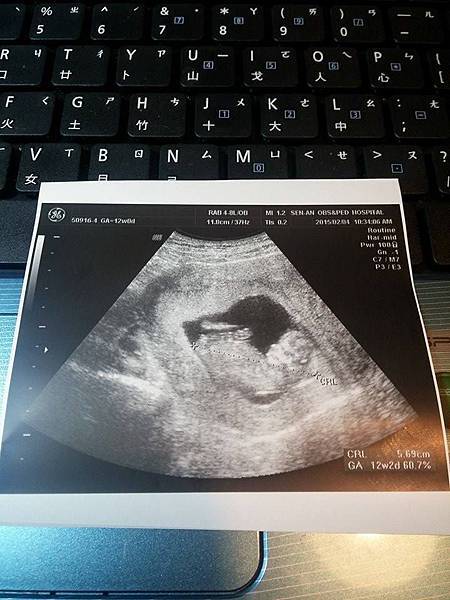

【2015.2.4~第五次產檢12W2D】~Dr.許

超音波看到小bebe,感覺就是好久不見啊!!

身長5.69公分,醫生快速地檢查過各器官說沒有問題,

我說我看不懂,醫生笑說不用看懂沒關係...

頸部透明帶也在標準值內,還笑說寶寶現在像外星人一樣(是真的啦~),